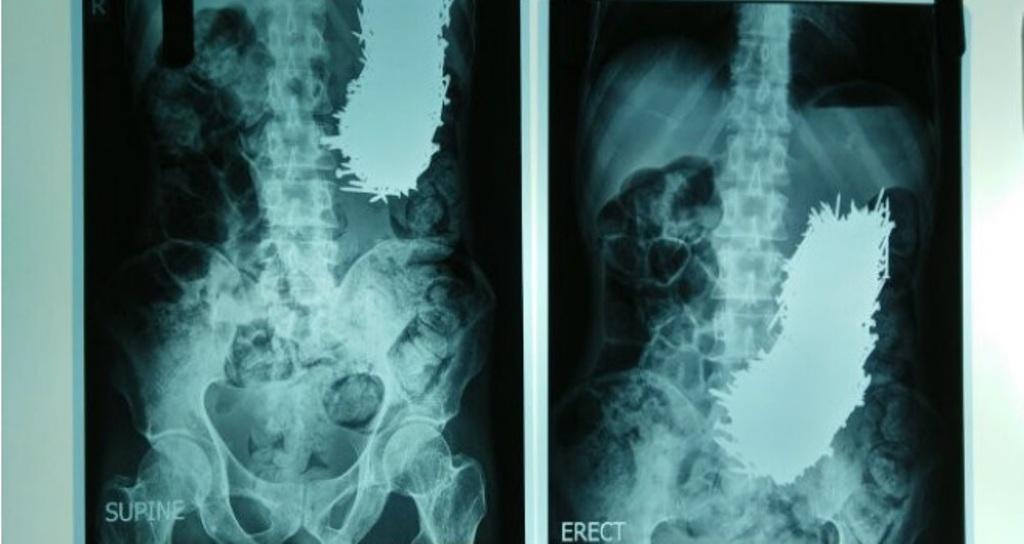

"Endoskopia zbuloi praninë e objekteve metalike në stomak. Vetëm pas fillimit të operacionit gjetëm, që stomaku i tij ishte plot me gozhdë të madhësive të ndryshme.

Operacioni zgjati rreth një orë e gjysmë dhe gozhdët që peshonin më shumë se një kilogramë u hoqën nga stomaku duke përdorur magnet. Është rast i rrallë. Nuk mund të kujtoj asnjë shembull të një numri aq të madh të gozhdëve në stomakun e një personi", u shpreh mjeku.